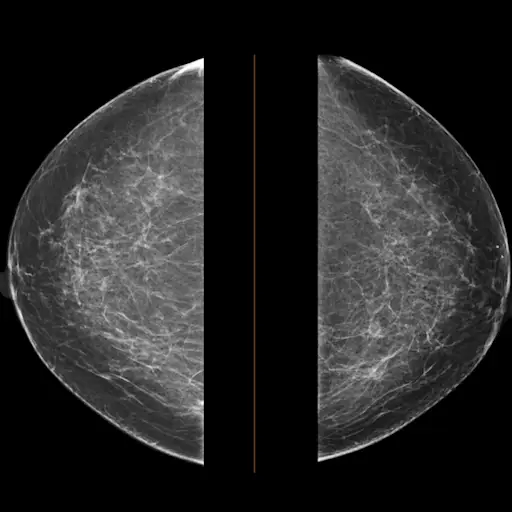

乳房活检中钛标记物的了解

如果你已经对你的乳房进行手术活检(或者你马上就要做),你可能会知道你的医生用一个很小的钛夹(芝麻大小)来标记检查过的癌症部位。如果你需要进一步的干预,这将识别出该区域。谢天谢地,五分之四的活检结果是阴性的。然而,不管是否消极,活组织检查都会带来副作用,包括手术后几个月的疼痛、灼烧和不适。现在,一些人在想:这应该归咎于视频吗?

波士顿Dana-Farber癌症研究所的乳腺外科肿瘤学家Laura Dominici博士解释说,在乳房活检中插入标记有几个原因。首先,它可以很容易地识别出可疑的地方,以便日后清除。多米尼西医生说:“如果他们的病理结果出来了,有人需要手术,我们希望能够可靠地再次找到那个斑点。”通常情况下,这个区域是很小的,但是一个夹子可以准确地指出你的胸部有问题的部分。

如果你的乳房部位被证明是良性的,钛夹就可以作为未来检查的指标,告诉医生那个部位已经检查过了,没有必要在同一个部位进行第二次活检。多米尼奇医生说:“这有助于放射科医生在未来知道乳房的哪些部位曾经接受过活检检查。”“他们能够看到这一点,并将其与之前的乳房x线照片进行比较,以确保没有变化。”